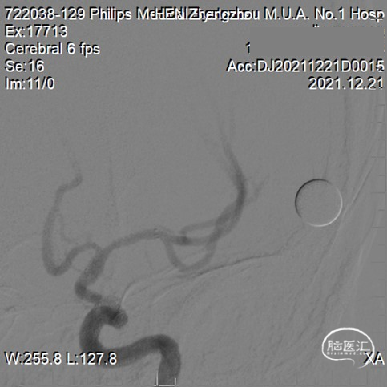

球囊扩张后随机Wingspan支架。

支架位置良好狭窄改善明显。

患者麻醉复苏良好,无出血及缺血并发症,安稳出院。